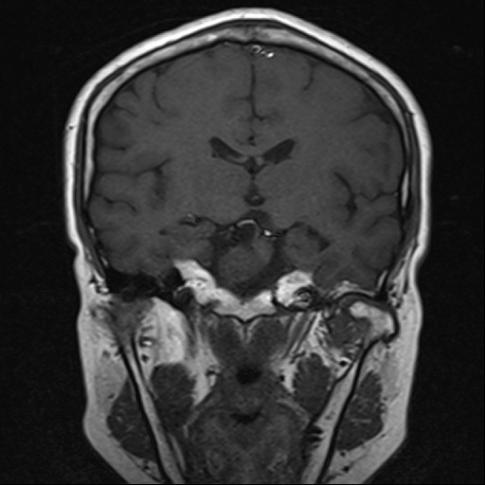

和大多数患者一样,家住郫都区的57岁的范女士也是如此。1年多前,范女士因面瘫行头部CT检查发现颅内鞍区占位。范女士当时认为占位病变不大,症状不重,又想到需要"开颅"动手术,这让她打起了退堂鼓,这一退便等了1年。直到2个月前,范女士开始出现视力下降的表现,并伴有头痛、头昏等不适,便到医院行头部MRI检查发现:鞍区占位较之前明显增大。这可将范女士愁坏了,立即和家人于6月份到郫都区人民医院神经外科就诊。本已做好开颅手术心理准备的范女士,却万万没有想到,医生既没有给自己开刀,也没有留下任何疤痕,就将颅内的肿瘤顺利切除了。

(术前检查发现肿瘤)